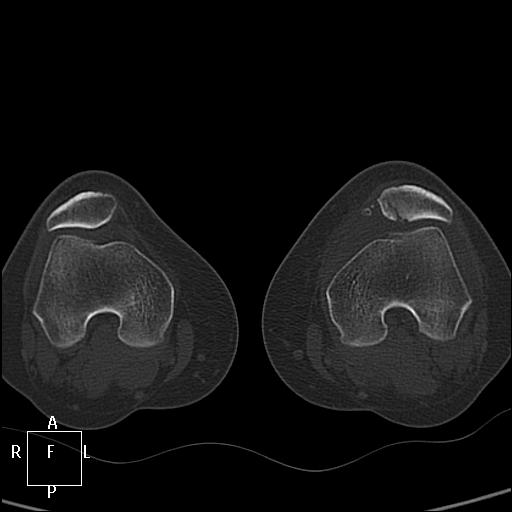

КТ коленных суставов. Травма. Женщина 31г

Наша врач, травма была в понедельник, подскользнулась и подвернула ногу, "думала, что пройдёт". Предыдущая травма в ноябре. Сейчас шикарный кровоподтек по внутренней стороне голени.

Публикации: 1749

А не могёт это быть варианом строения надколенника, в том смысле не ужели можно подвернув ногу (без удара) разорвать надколенник , как мне увиделось только суставная поверхность повреждена..??А кровоподтек от разыва связок.. хотя скиалогически подумал бы о переломе.. Или это неполный перелом на фоне аномалии..

Особый вариант перелома – вертикальный, при котором линия перелома проходит сверху вниз. В подавляющем большинстве случаев такие переломы не смещаются, так как тяга мышцы направлена снизу вверх, то есть вдоль линии перелома.   ( http://travmaorto.ru/103.html )

Скорее всего при подвороте стопы произошел отрыв медиальной связки надколенника. http://www.sportmedicine.ru/knee_norm.php

При вывихе надколенника кнаружи происходит отрыв медиального связочного аппарата, иногда с фрагментом надколенника. А вывих вправляется самостоятельно.